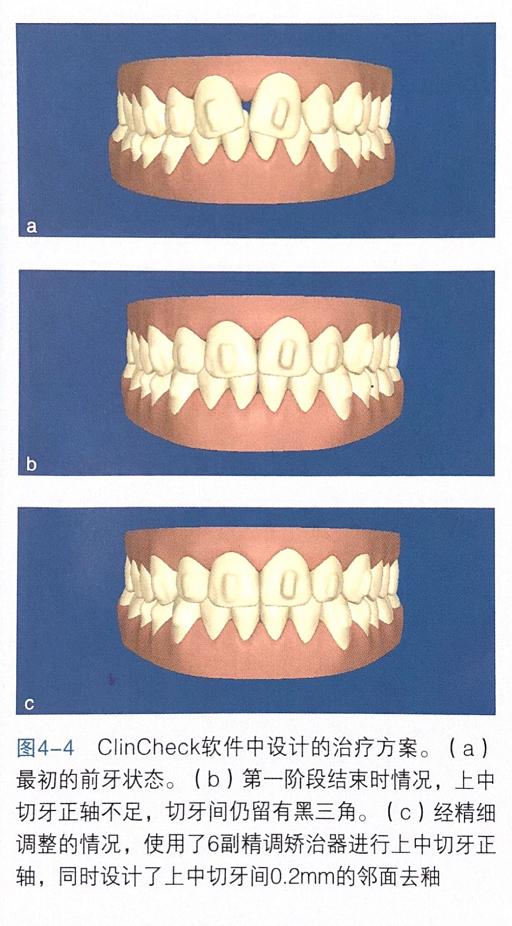

ClinCheck软件中的治疗方案

口内像